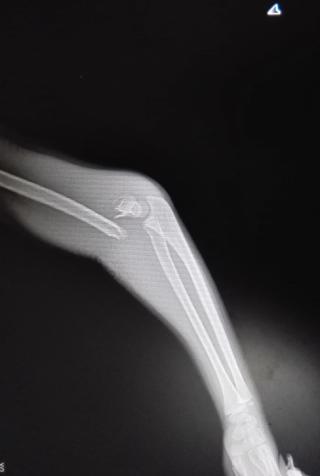

典型病例:中醫(yī)手法整復(fù),夾板固定治療肱骨髁上骨折